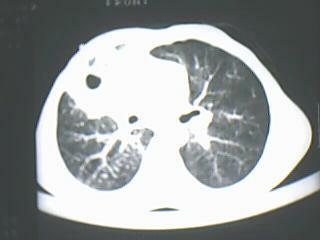

以下是引用随光逐影在2009-8-7 15:40:00的发言:[br]考虑右肺继发性肺结核并右肺上叶空洞形成,两肺支气管播散;不排除右肺上叶空洞内霉菌感染可能。

以下是引用jiangjing在2009-8-7 14:38:00的发言:[br]右上肺张力空洞,酐珞坏死灶,支气管扩张,多发播散灶,纵膈淋巴结显示,胸膜增厚---结核